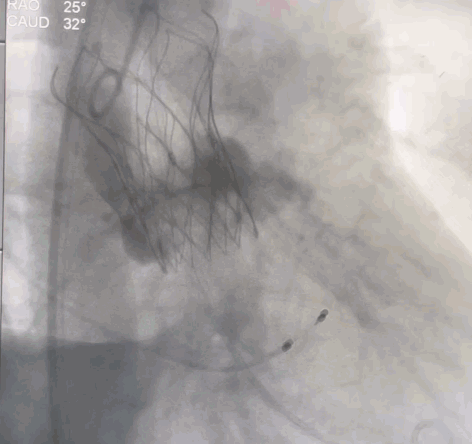

术中操作

经右侧颈动脉途径,直头导丝跨瓣成功后送入猪尾导管至左室,置入22F动脉鞘管。结合术前CT,装配好VitaFlow Liberty™27号瓣膜,在加硬导丝支撑下,送导管输送系统至主动脉根部并跨过主动脉瓣口,主动脉根部造影,确认瓣膜处于理想位置,在起搏下,经过慢释放、快释放及终释放,完成瓣膜释放过程。术后病人生命体征平稳,跨瓣压差明显改善,无瓣周漏。

瓣膜定位

瓣膜释放中

瓣膜释放完成

瓣膜形态良好,无瓣周漏